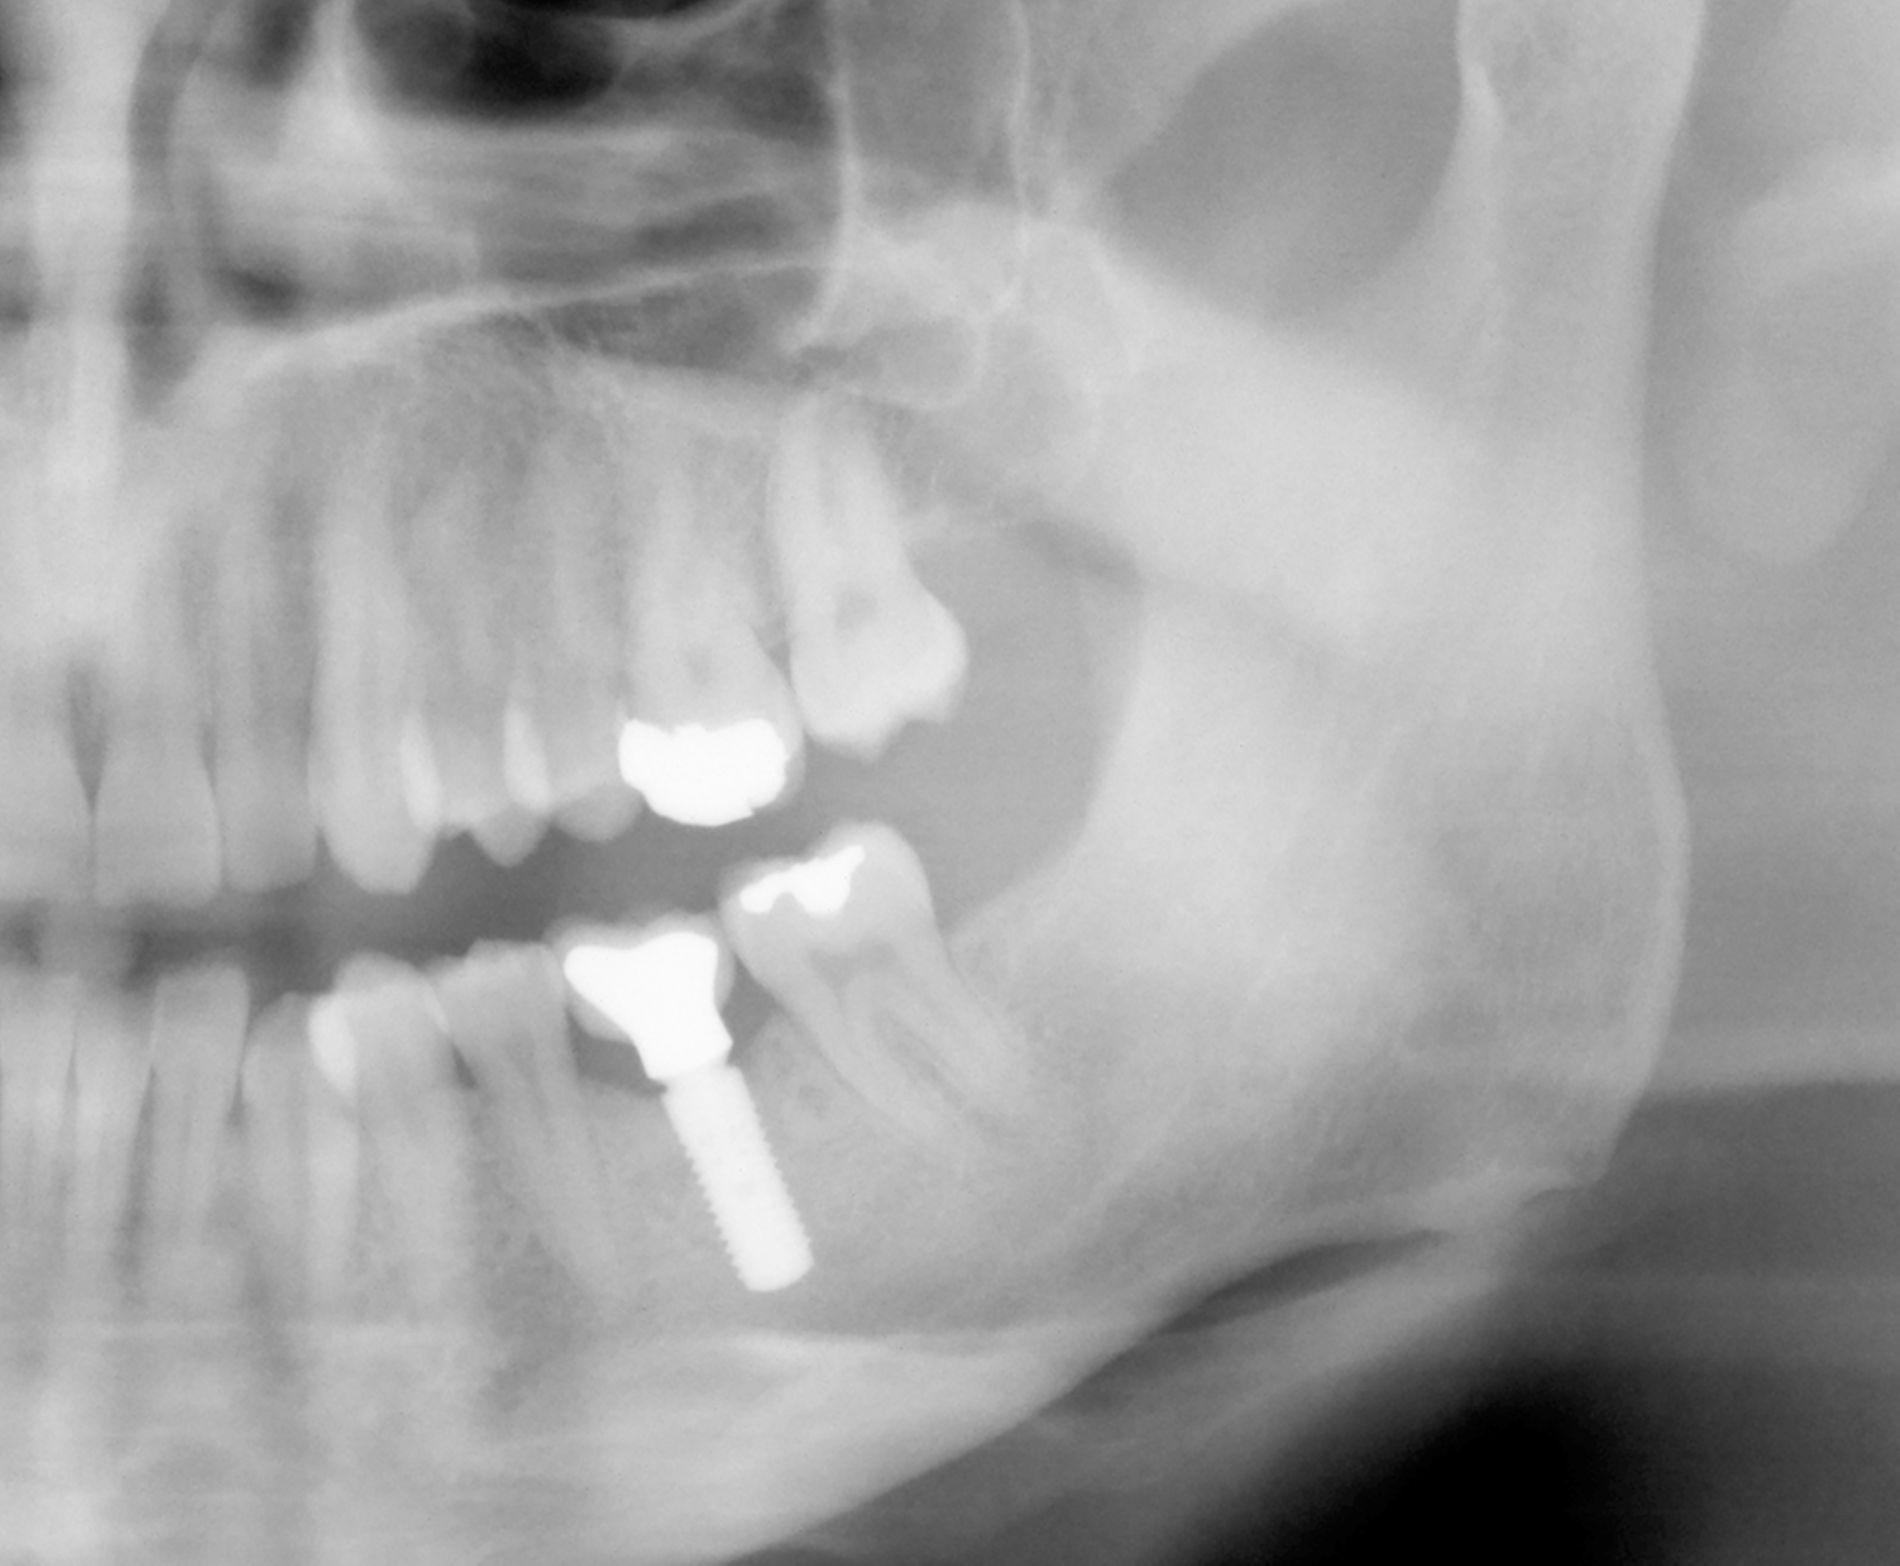

Der Erfolg der Wurzelspitzenresektion beinhaltet den In-situ-Verbleib des Zahns, die Symptomfreiheit und eine röntgenologische Ausheilung des knöchernen Defekts (Abbildung 1). Der erste Punkt dient als Grundlage für die Berechnung der Überlebensrate, alle Punkte zusammen dienen der Berechnung der Erfolgsrate. Literaturangaben zur Prognose wurzelspitzenresezierter Zähne sind ausreichend vorhanden und unter Berücksichtigung der jeweiligen Nachbeobachtungszeiträume (1 bis 10 Jahre) erscheinen die Überlebens- beziehungsweise Erfolgsraten (47,5 bis 91,5 Prozent) (Tabelle 1) akzeptabel, insbesondere vor dem Hintergrund der Tatsache, dass die WSR oftmals die allerletzte Therapieoption für einen Zahn darstellt.

Eine präoperative akute klinische Symptomatik in Form von Schmerzen, Perkussionsempfindlichkeit, einer Schwellung oder einem Abszessgeschehen ist mit einer signifikant schlechteren Prognose des Zahns vergesellschaftet. Gleiches gilt für das Vorhandensein einer Fistel bei chronischem Verlauf. Zähne, die zum ersten Mal einer WSR unterzogen werden, haben eine signifikant bessere Prognose als Zähne mit einer Revision der WSR. Ein weiterer wichtiger prognostischer Faktor sind retentive Wurzelstifte (Abbildung 3). Die besondere Problematik bei diesen Zähnen liegt oftmals in der erschwerten Möglichkeit der apikalen Abdichtung, wenn der Stift bis zum Neoapex reicht. Infolgedessen werden die Wurzeln oft weniger stark gekürzt, um noch ausreichend Wurzelkanal für die retrograde Wurzelfüllung zu haben. Zum anderen werden in dieser Gruppe auch in der Folgezeit Wurzelfrakturen häufiger beobachtet. Dies scheint insgesamt von Relevanz zu sein, denn diese Zähne haben ebenfalls eine signifikant schlechtere Prognose. Zähne mit einer Stiftperforation stellen ohnehin eine Kontraindikation für eine WSR dar und sind hier gar nicht berücksichtigt.